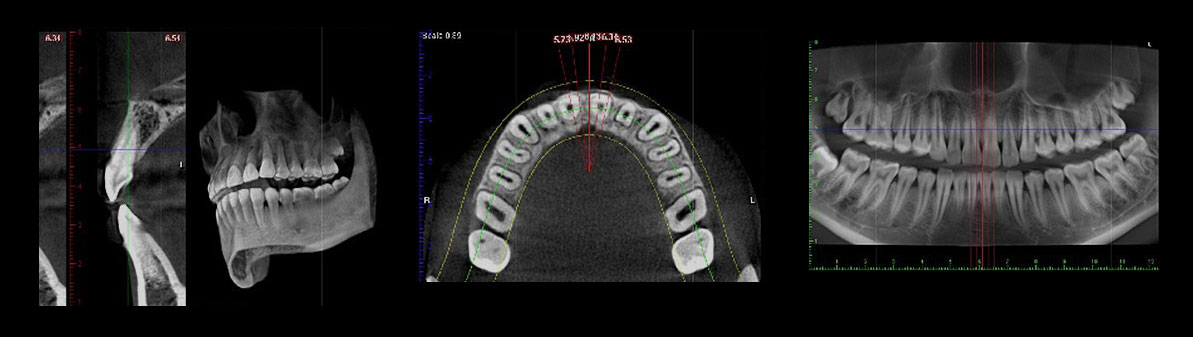

パノラマ(保険適用)、セファロそして歯科用CT撮影を可能としたフィンランド・プランメカ社のProMax 2D/3Dを採用したデジタルX線撮影による診断を行っています。

通常のX線被爆量の70%以上も低減しますので、妊婦の方でも安心して検査していただけます。

フィンランド・プランメカ社のProMax 2D/3Dの導入により、従来の2次元的な平面のみのX線画像では撮影できなかった詳細を、3次元の立体画像で撮影することが可能です。顎の内部構造、顎や歯だけでなく上顎洞(鼻の奥)の形態や粘膜の状態、病巣などを立体的に把握し、正確な診査・診断を可能とするため、インプラントだけでなく、矯正、親知らず、根管治療など、幅広い歯科治療において治療の安全性を高めます。

インプラント治療

埋入する部位の術前の骨の状態(質や厚み、高さ、形態など)を正確に診断し、的確な治療計画をたてることにより、質の高いより安全な治療を実現します。

矯正治療

顎骨の状態から歯の移動の限界が予測できるため、効率の良い治療計画のご提案を実現します。また、現在では矯正用インプラントを固定源として、より正確かつ短期間で矯正治療を行う手法もあり、CT撮影による診断は患者様の選択肢をも拡大します。

歯周病治療

骨の破壊の程度などをより詳細に把握することにより、おおよその歯の寿命の積算が可能となり、非常に予知性の高い治療を実現します。

親知らず

抜歯部位を立体的に把握することにより、神経を引っ掛けてしまう可能性、周囲の炎症の程度、病巣の有無や大きさや位置、埋伏歯の位置なども精密に判断・考慮して治療を行うことができるため、余分な切開や骨の切削などを回避できます。

根管治療

歯根の先端の病巣発見や、治療後の治癒の状態などの正確な把握によって、根の病気の完治を目指しやすくなります。